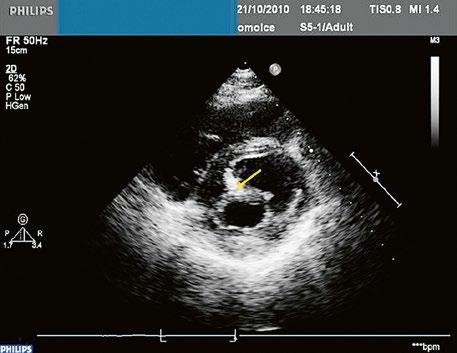

Poslechový nález systolického šelestu nad plicnicí s fixním rozštěpem 2. ozvy je nenápadný. Echokardiograficky je patrná dilatovaná a objemově přetížená pravá komora s paradoxním pohybem septa (Obr. 45.9), zkratový tok může být vidět i transtorakálně (TTE) (Obr. 45.10, Video 45.3, Video 45.7), ale suverénní diagnostickou metodou je jícnová echokardiografie (TEE), případně s 3DE zobrazením (Obr. 45.1, Obr. 45.2,

Obr. 45.10 TTE, čtyřdutinová apikální projekce s levo pravým zkratem na úrovni síní (šipka) při defektu septa síní typu secundum PK – pravá komora, LK – levá komora, LS – levá síň, PS – pravá síň